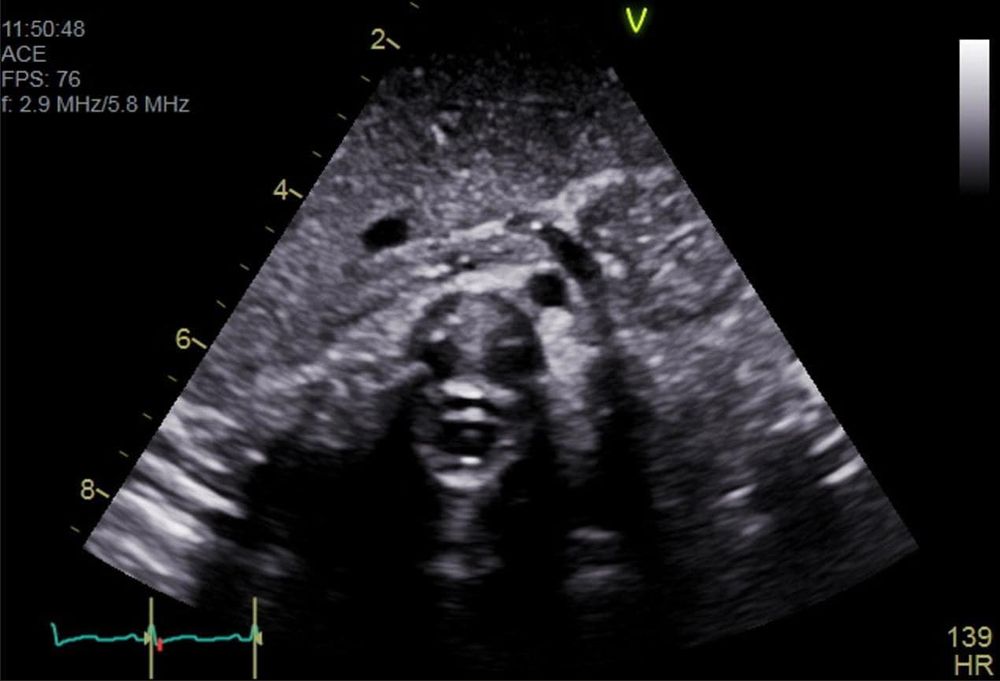

This next #SpookyEcho is doing its best Halloween Phantom impression! 🎃

This is a TTE showing a multilobed mass in the right atrium.

Do you see the face at the center of the image? 😱 #SpookyEcho

This is actually the spinal column as viewed from the subcostal situs sweep in a pediatric congenital echo.